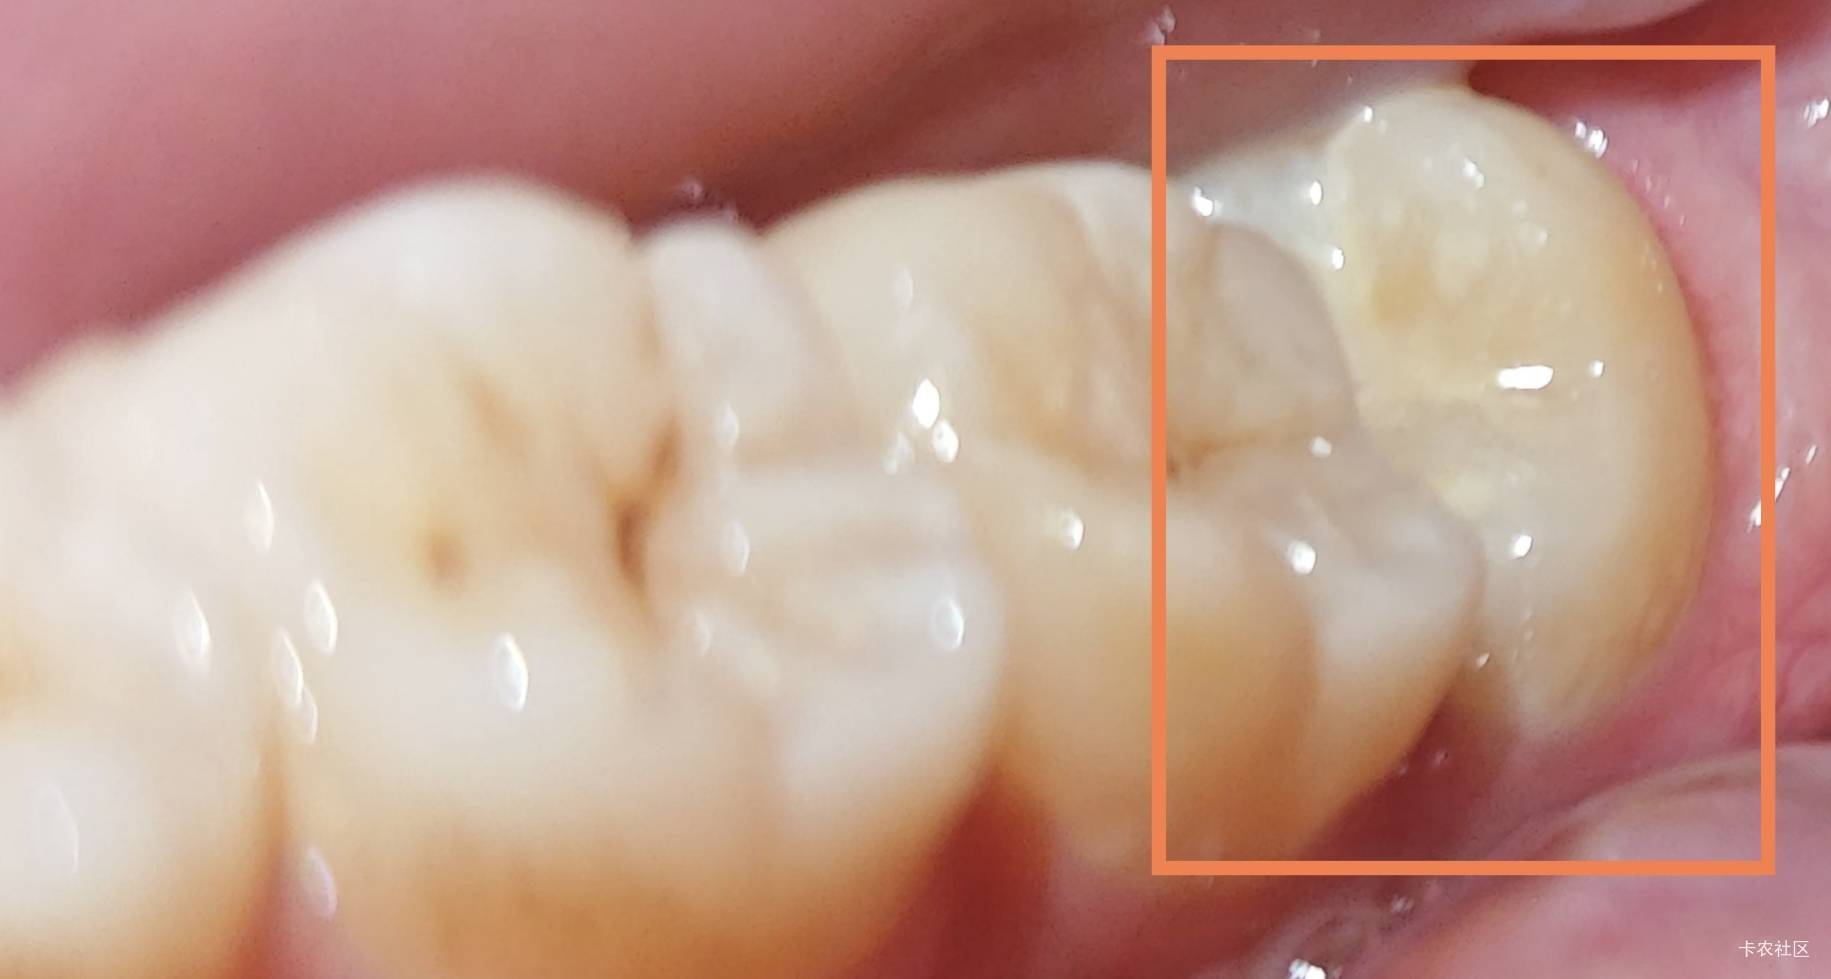

左下的这个智齿长的歪,几个月了,这两天才有点疼,应该是长完整了顶到我另一颗牙了,

左下的这个智齿长的歪,几个月了,这两天才有点疼,应该是长完整了顶到我另一颗牙了,去拔不知道要花多少钱不太敢去左下的这个智齿长的歪,几个月了,这两天才有点疼,应该是长完整了顶到我另一颗牙了,69 / 作者:暖风归去 /